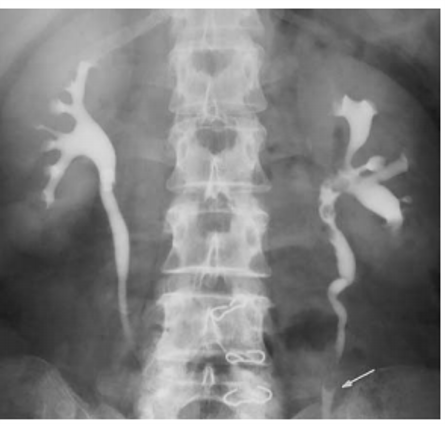

multifocal TCC